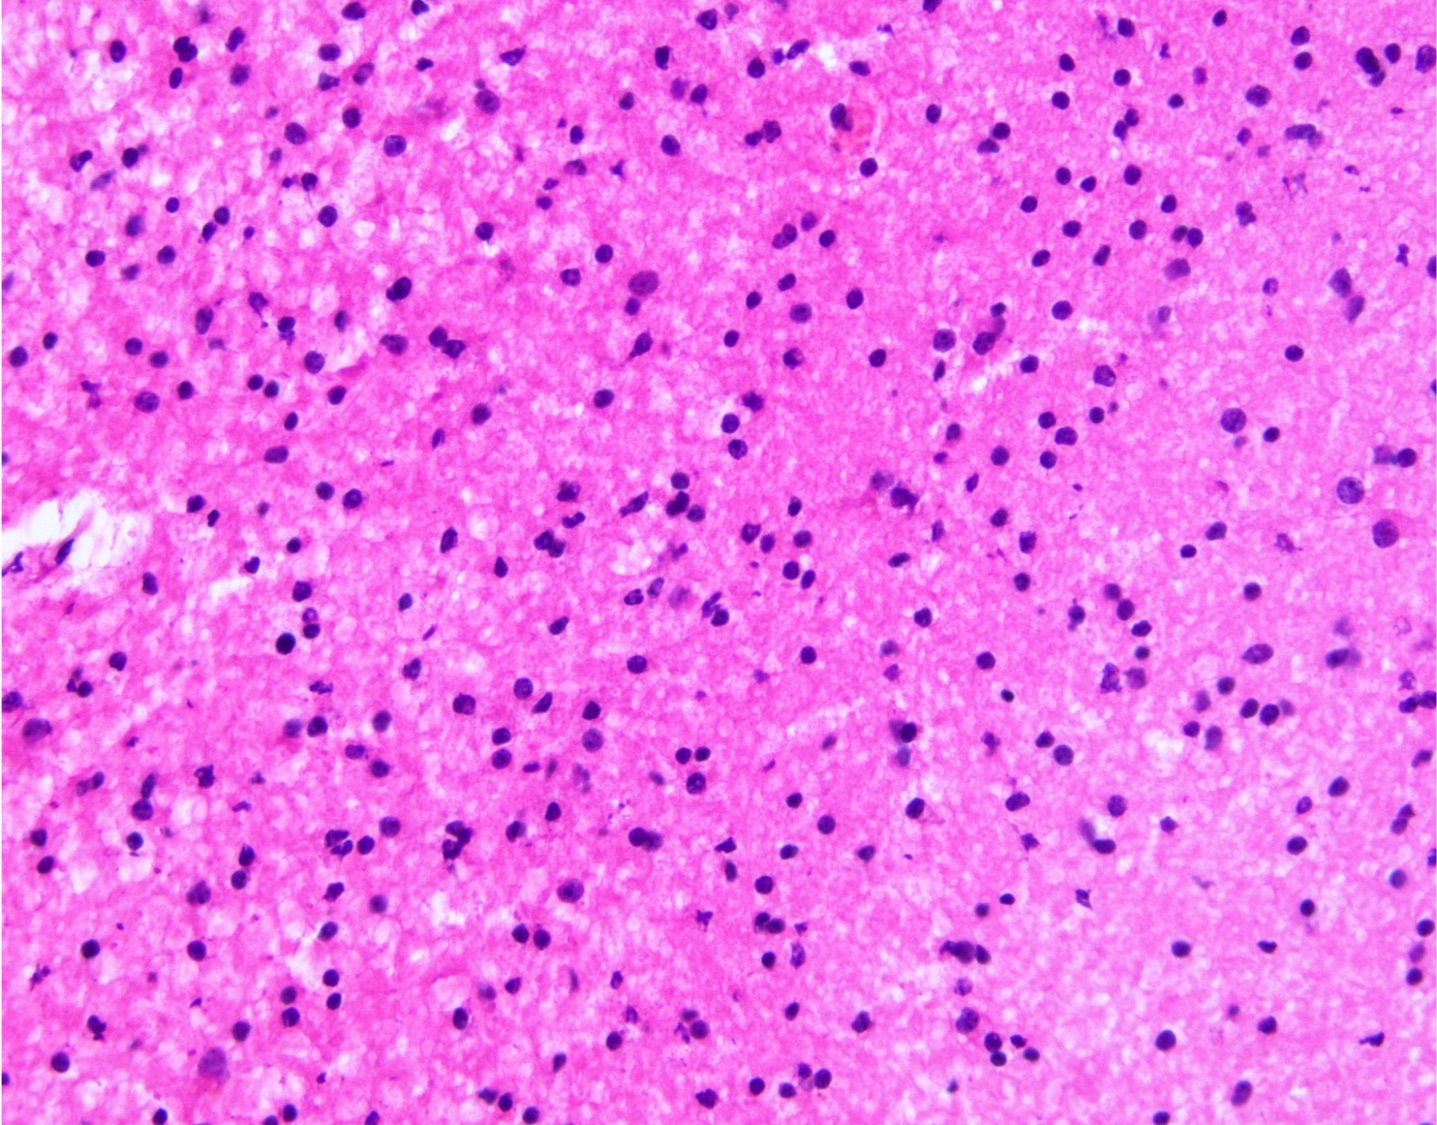

Microscopic (histologic) description

- Closely packed cells with small, round, monotonous nuclei (slightly larger than a normal oligodendrocyte)

- Perinuclear clearing (fried egg appearance)

- Formalin fixation artifact

- Will not be seen on frozen sections or smear preparations

- Network of thin walled, branching blood vessels (chicken wire vasculature)

- Microcalcifications (calcospherites) are characteristic

- Presence of perineural, perivascular or subpial aggregates of tumor cells (secondary structures of Scherer)

- Occasional mitoses and moderate nuclear atypia are still consistent with grade 2 designation (J Neuropathol Exp Neurol 2001;60:248)

- Not uncommon to find well differentiated / fibrillary astrocytic morphology (Acta Neuropathol 1984;64:265)

Microscopic (histologic) images

Contributed by Jared T. Ahrendsen, M.D., Ph.D. and John DeWitt, M.D., Ph.D.